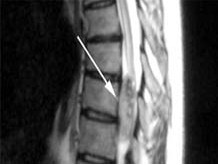

【手術(shù)圖片】

椎管內(nèi)腫瘤 椎管內(nèi)腫瘤術(shù)中